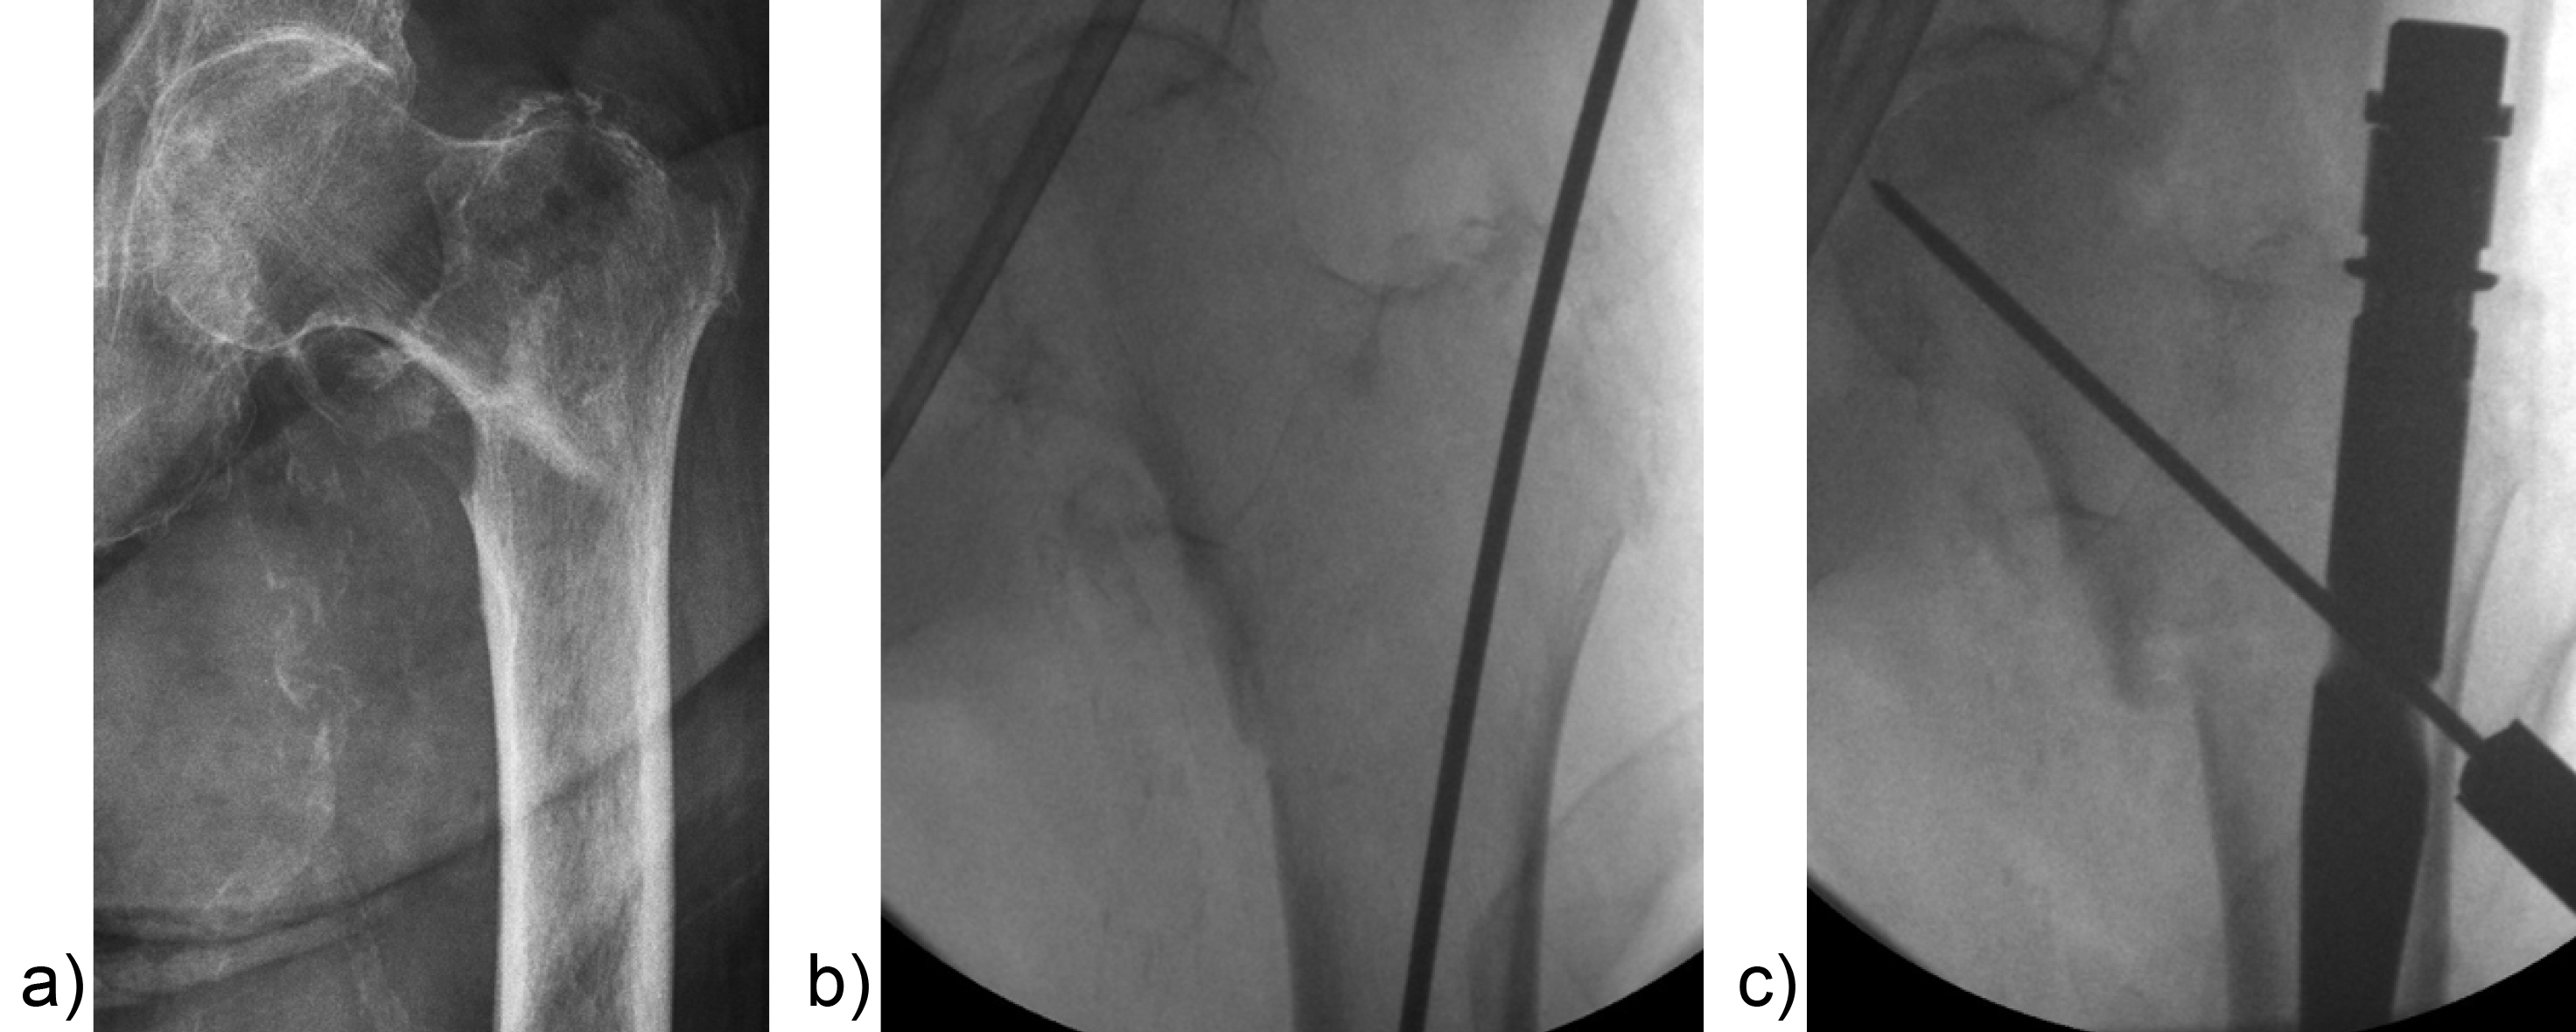

An 83-year-old female patient sustained a 31-A.2.2 fracture of the right proximal femur after a fall at home (Figs 1-2). Intraoperative and postoperative images are shown (Figs 3-5).

A 98-year-old female patient sustained a pertrochanteric fracture of the left proximal femur due to fall in her nursing home (Fig 1). There was significant pain and coxarthritis in the right hip, and hypertension. Surgery was performed within 24 hours. There was an indication for augmentation due to the instability of the fracture. The patient additionally suffered from osteoporosis and dementia.